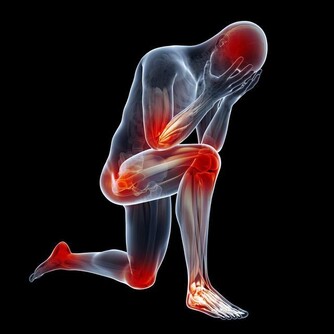

而針扎的刺痛或者是“按著疼”的感覺往往跟心臟關係不大。3.疼痛:相比較而言,疼痛反應是猝死的發病徵兆中,最易被我們抓住和感知的信號。

當感到胸部出現劇烈、緊縮、壓榨性的疼痛,且感到透不過氣時,就要提高警惕。4.重度的血壓升高:對於主動脈夾層患者,發病徵兆是劇烈疼痛,而且在疼痛的同時會伴有重度的血壓升高。

5.憋氣、口唇發紫:如果工作性質是久坐或長期站立,血液循環不好,

當病情發作時,除了疼痛外,

若還有憋氣、明顯的紫紺、口唇發紫、血氧下降等,就要高度懷疑可能是肺栓塞。